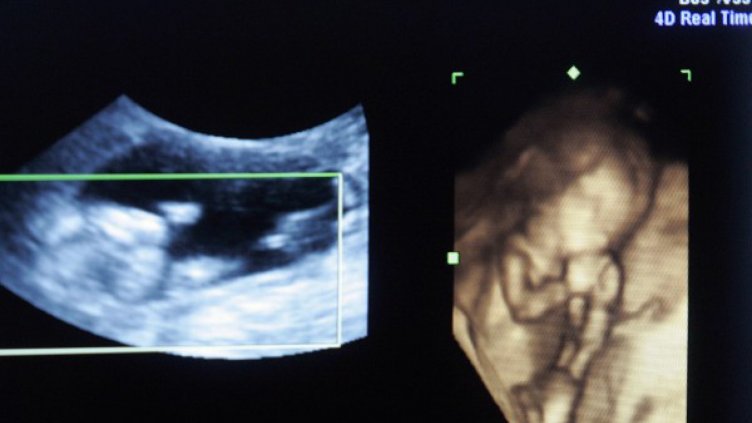

Момченце получи своят шанс за живот благодарение на уникална операция, извършена от д-р Кристина Чачева и нейния екип в МБАЛ "Надежда".

В утробата на майка си то споделяло обща плацента със своя еднояйчен близнак без сърце – т. нар. "паразитен близнак".

Тъй като единият близнак няма развити сърдечни структури, другият го кръвоснабдява и по този начин с напредване на бременността и наедряване на паразитния близнак здравото бебе е изложено на сериозна заплаха да развие сърдечна недостатъчност.

За да се спаси здравото бебе, е предприета вътреутробна операция в 15-ата седмица от бременността.

След успешната интервенция бременността на жената е проследена от екипа на д-р Чачева и благодарение на общите им усилия бебето се ражда здраво и доносено в 38-а гестационна седмица.